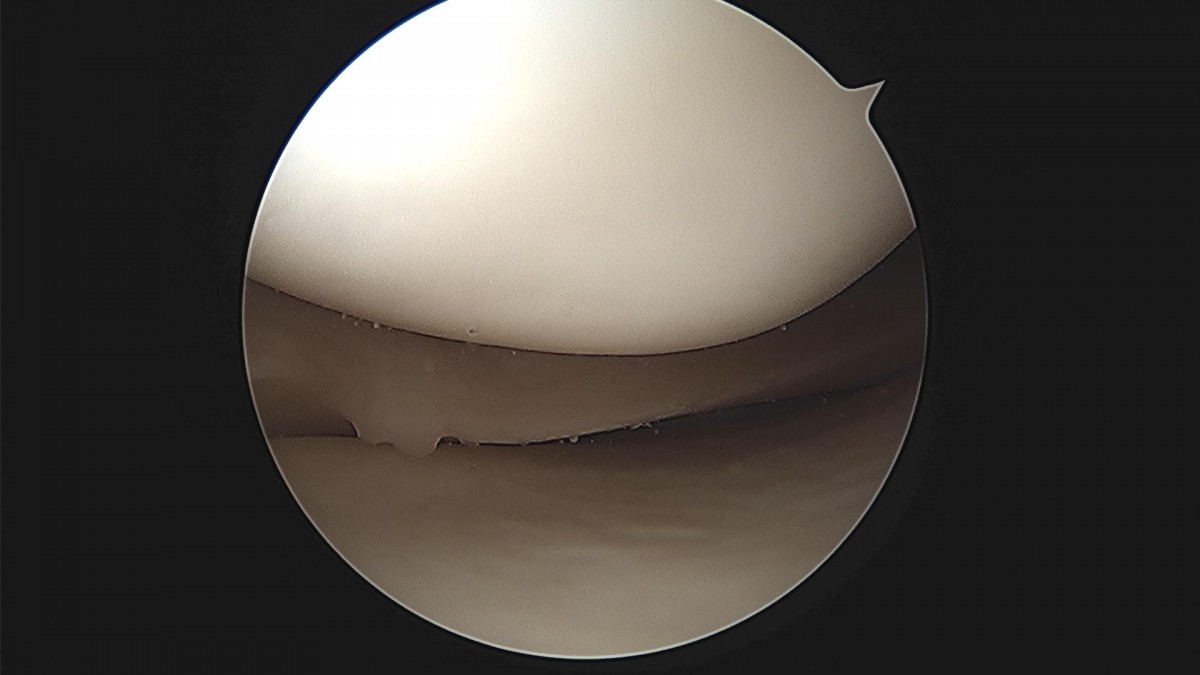

배우한 원장님 무릎 반월상 연골판 봉합술 홍재O 환자

d4279b3b94d98ed627b1644855bcf9f2_1699601484_4621.jpg